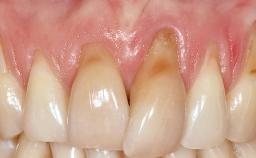

It is sometimes necessary to remove and replace compromised implants. This case is a clear example of the need for multiple steps to achieve an optimal therapeutic result for patients with non-salvageable implants. It illustrates how the lost soft and hard tissues were rebuilt in a sequence that improved the healing of the hard tissues and assured their long-term stability. The 35-year-old healthy patient presented with clinical attachment loss on the proximal and lingual surfaces of the natural dentition. Some gingival recession was present on natural teeth, particularly in the posterior sextants (S1, S3, S4, and S6).

Soft Tissue Anatomy Intact Defective

Bone Volume Horizontally and vertically sufficient Horizontally deficient Deficient vertically or deficient vertically AND horizontally